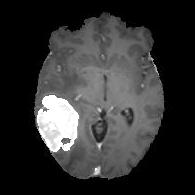

We argue that the sub-optimal paradigm of processing different abstractions within a single CNN pipeline can be remedied through the effective processing of information in a structured manner. Consequently, we devise strategies for disentangling the edge and texture information within a single training pipeline. Figure 2 illustrates how our proposed module, dubbed EG-CNN, can be paired with any existing CNN encoder-decoder to improve segmentation quality near intensity edges. We have applied our EG-CNN to the tasks of brain and liver tumor segmentation in medical images (Figure 3).

(1) Brain MR (2) Liver MR (3) Liver CT (4) Lung CT